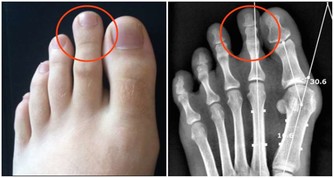

多發性骨髓瘤是一類會抑制人體生產出健康血細胞的癌症。臨床研究表明,多發性骨髓瘤會損傷到患者身體的多個部位,常見的是脊椎、顱骨、骨盆,以及肋骨。在發病初期,患者可能不會出現任何異常症狀。

隨著病情惡化,患者逐漸會感到自己的骨頭在隱隱作痛,骨骼似乎非常脆弱,而且會感到疲倦乏力,刷牙時也會引起牙齦出血,女性患者在經期間的排血量也會異常增多。